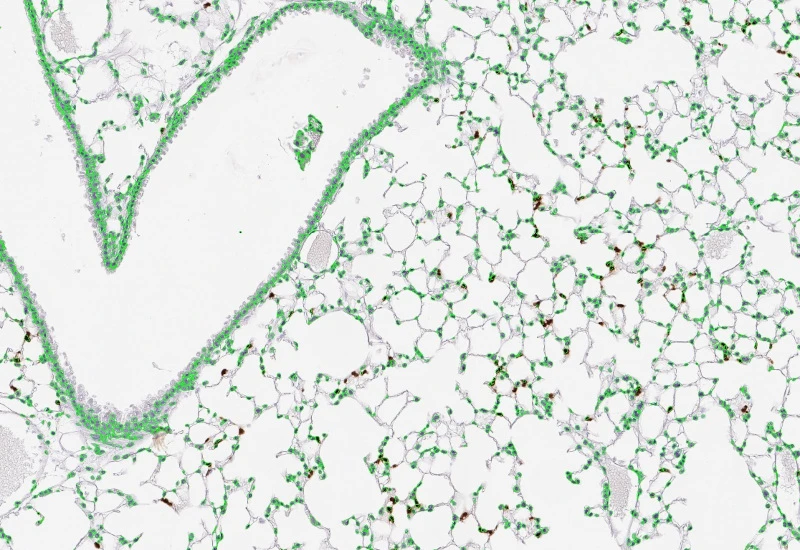

Segment nuclei and lung metastructures (total tissue, bronchioles, vessels, alveoli), detect cellular phenotypes within each component, and measure up to 20 morphometric parameters per metastructure and nucleus.

The Pulmo App segments nuclei as well as the metastructure components of lung, including total tissue, bronchioles, blood vessels and alveoles. Further it detects cellular phenotypes within the metastructure components. Each segmented metastructure/nuclei is measured for up to 20 morphometric parameters.